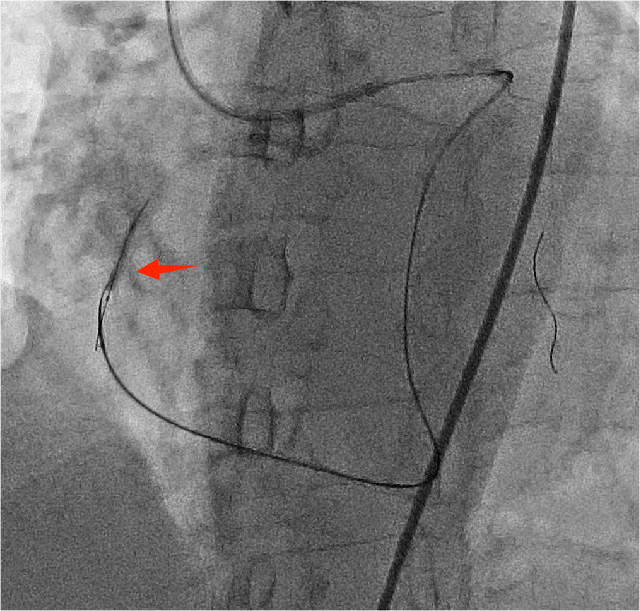

4月24日,朱舜明副主任医师为患者制定周密的手术方案和风险处理方案,朱舜明副主任医师、唐治国主治医师、张翔主治医师、张豪住院医师开展持续3小时的介入手术。术中穿刺桡动脉和股动脉,双路径同时造影显示病变血管完整结构,开展Reverse-CART技术,将逆向导丝送入正向指引导管,跟进微导管,交换导丝后用球囊扩张病变,沿逆向导丝送入双腔微导管至闭塞血管远端,沿双腔微导管送入正向工作导丝至右冠后降支,并退出逆向微导管和导丝,采用血管内超声精细评估病变情况,最终向右冠状动脉内植入3枚支架。术后多体位造影未见残余狭窄及贴壁不良,完美结束手术。

图2 Reverse-CART技术逆行导丝通过右冠病变血管,红色箭头:病变部位